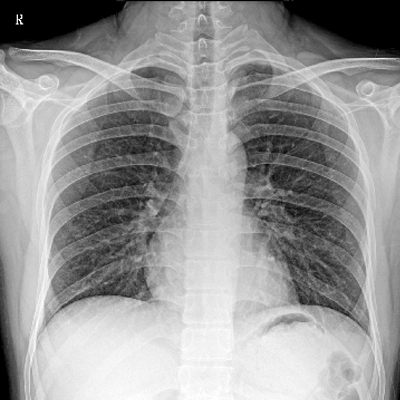

Clinical picture

臨床圖片